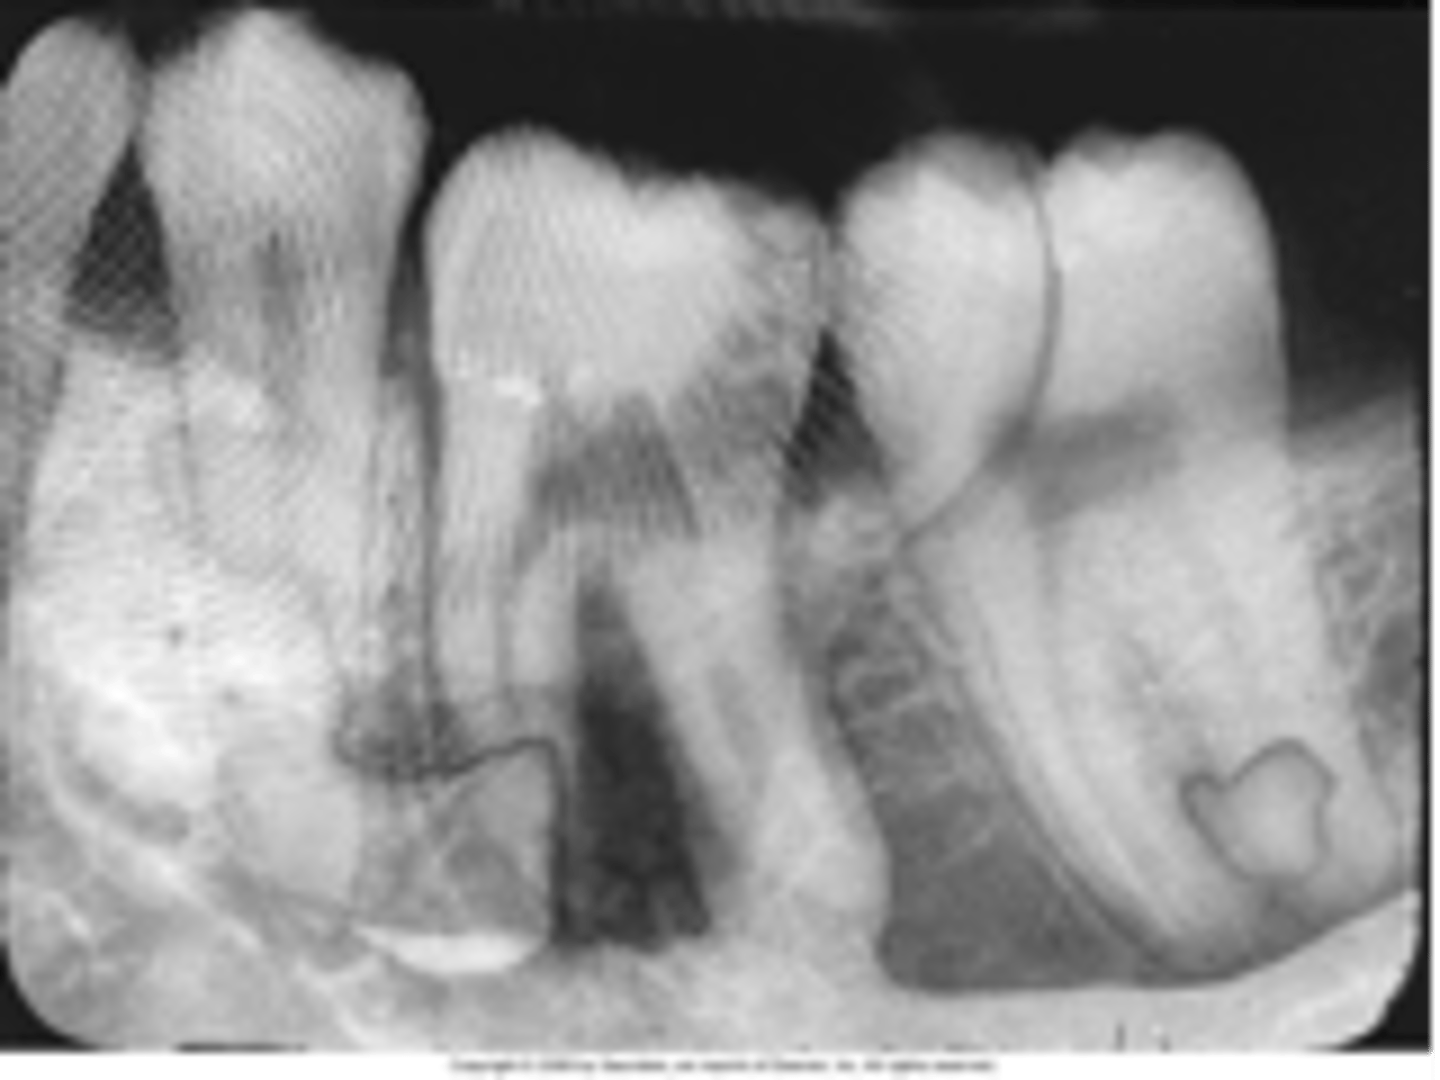

Film bending

Film creasing